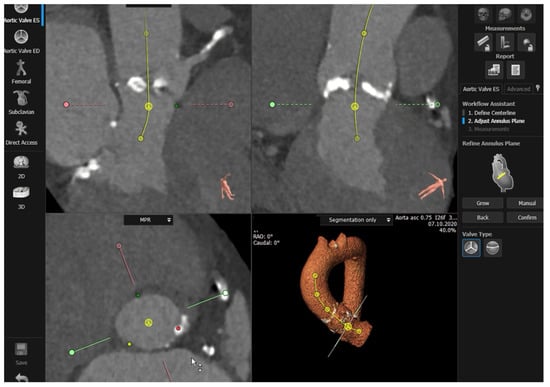

2. Aortic Root Assessment

2.1. Aortic Annulus

3.2.2. Semi-Automated and Automated Sizing

4. Echocardiography